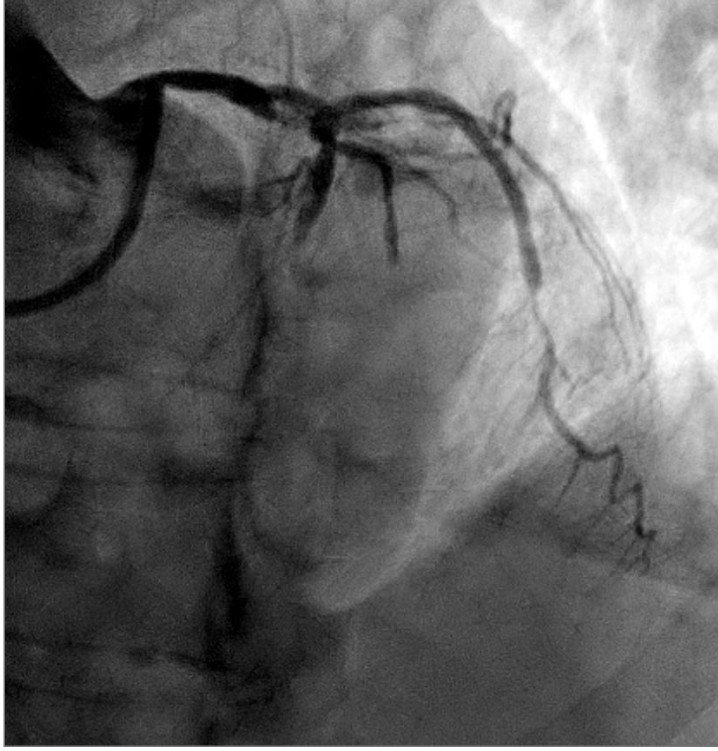

Angiogram showed culprit total occlusion of the proximal LAD.

Despite PCI, cardiogenic shock progressed on the cath lab table. Impella was used, and the patient was intubated for progressive respiratory failure.

Ultimately he died.

Although his mortality risk was high even before arrival, there was an hour of misdiagnosis. One hour delay can results in loss of up to 50% of the mortality benefit of reperfusion. It is possible he could have had a better outcome if he had reperfusion 1 hour earlier.